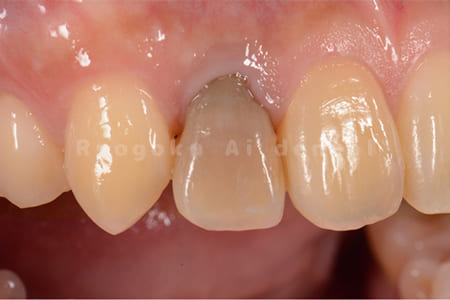

Case04

-

- 原因

- 失活による歯牙変色

- 治療内容

- ブリーチング+マイクロエンド+ダイレクトボンディング+ホワイトニング

- 治療費用

- 231,000円(ブリーチング55,000円+マイクロエンド77,000円+ダイレクトボンディング66,000円+ホワイトニング33,000円)

結婚式前に前歯を綺麗にしたいとのことでご来院された患者様です。根の状態も悪かったためマイクロスコープ下で根管治療を行い、ブリーチングの後にダイレクトボンディングで形態修正を行いました。